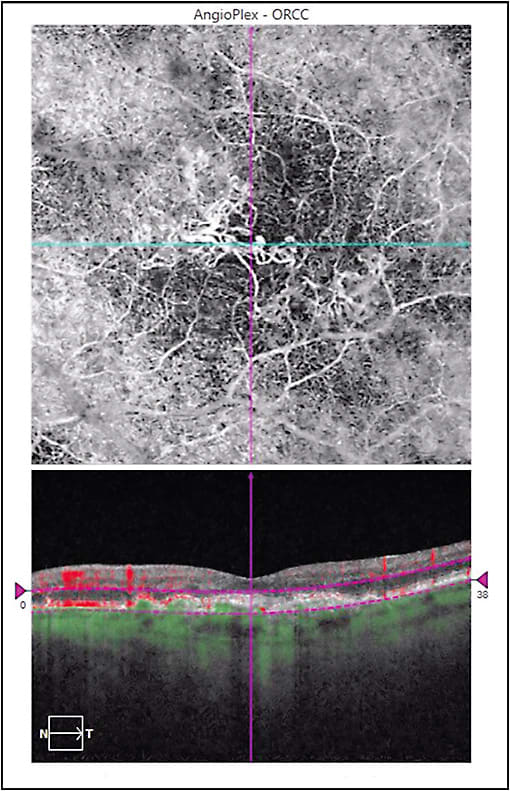

OCT angiography (OCTA) is a noninvasive method that uses red blood cell phase decorrelation technology with high frequency scanning to indirectly visualize blood vessels in a 3-dimensional manner, revealing the trilaminar (superficial, intermediate, and deep) retinal capillary plexus, areas of retinal capillary nonperfusion, intraretinal microvascular abnormalities, and retinal neovascularization. In addition, OCTA can show pathologic choroidal neovascularization (CNV) (Figure 1), and it may discriminate type 1 from types 2 and 3 CNV. Limitations include inability to visualize lesions with slow flow, like retinal microaneurysms and polyps in polypoidal choroidal vasculopathy. Because there is no interference from leakage (which is not detected), vascular anatomy can be shown in stunning detail.